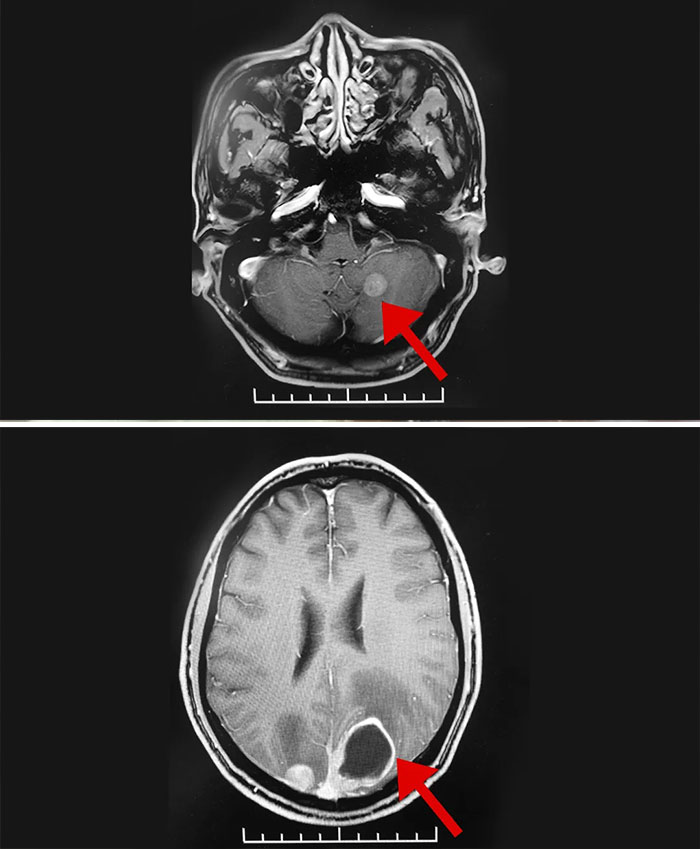

▲ 患者左側(cè)小腦半球、雙側(cè)枕葉多發(fā)轉(zhuǎn)移瘤

臨床磁共振檢查結(jié)果顯示:李老伯左側(cè)小腦半球、雙側(cè)枕葉多發(fā)轉(zhuǎn)移瘤,中度高顱壓,結(jié)合其已有頭痛等癥狀,需盡快干預(yù)治療。